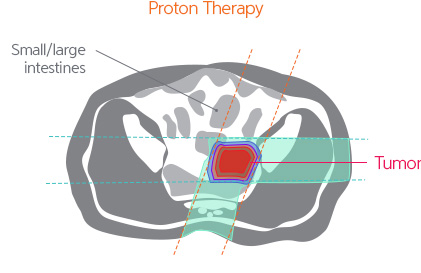

Proton cancer decreases concerns of side effects associated with radiotherapy retreatment and high dose radiation treatment while transferring a sufficient amount of radiation to obtain high tumor control rates.

For recurrent rectal cancer that has been previously treated with radiotherapy, it is known that tumor removal is difficult and that there are limitations in the cosmetic and functional aspects when treated with surgical operations. Therefore, there are many cases where high dose radiotherapy is implemented. In such cases, even if treated through intensity modulated radiotherapy, side effects from radiation exposure to the surrounding normal organs are common, and for 5 years, the tumor control rate has been less than 50%. However, proton treatment is expected to decrease the level of radiation exposed to the surrounding normal tissues while transferring a high dose of radiation to the tumor for effective removal.

Outcomes of proton treatment implemented on rectal cancer patients are not prevalent. However, when observing the outcomes of corpuscular radiotherapy, which have similar characteristics to the proton treatment, it reported a tumor control rate of over 90%.